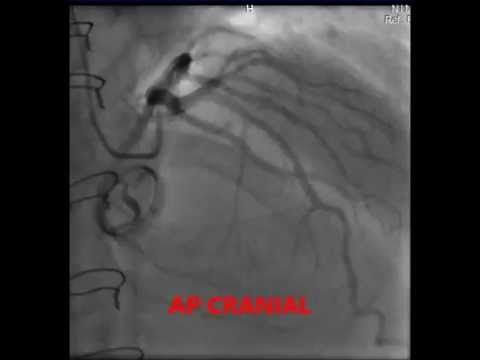

Medtronic hall valve in aortic valve position Fluoroscopy